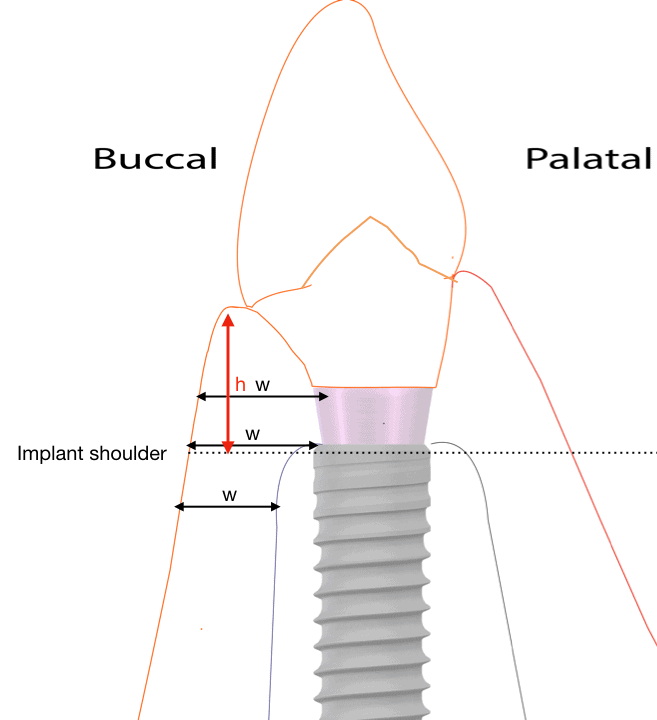

The Supracrestal complex is defined by the soft tissues and as such , the vertical height, the width (thickness) and overall morphology / consistency of the soft tissues is critical for the final long term success of our outcomes! A critical pre-assessment therefore includes the questions:

Nr. 4: Position yourself for success !

The correct 3-dimensional implant position is essential for everything else to work Compromised implant 3D position is the “root of all evil” leading a chain reaction of compromise in the restorative design and finally maintainability. Knowing the limitations from the beginning and decide the strategy that will allow us the perfect placement is an art and a science combined.

The “emergence profile” is a key for long term success and its optimal shape and size is crucial. Depth or height, Concavity or Convexity, angles of emergence, these are all design features we need to plan in advance before the implant is even placed. Otherwise, compromise and trouble is inevitable.